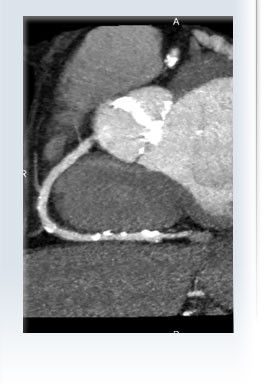

Kalk-Score-Messung

Wie hoch ist Ihr Herzinfarktrisiko?

Eine ausgezeichnete Antwort gibt Ihnen die Herzkranzgefäß-Kalk-Messung

Die Kalk-Bestimmung kann nicht feststellen wie stark ein Gefäß eingeengt ist. Siehe Cardio-CT.

Ärzte am Neumarkt   Cardio CT Celle 2009